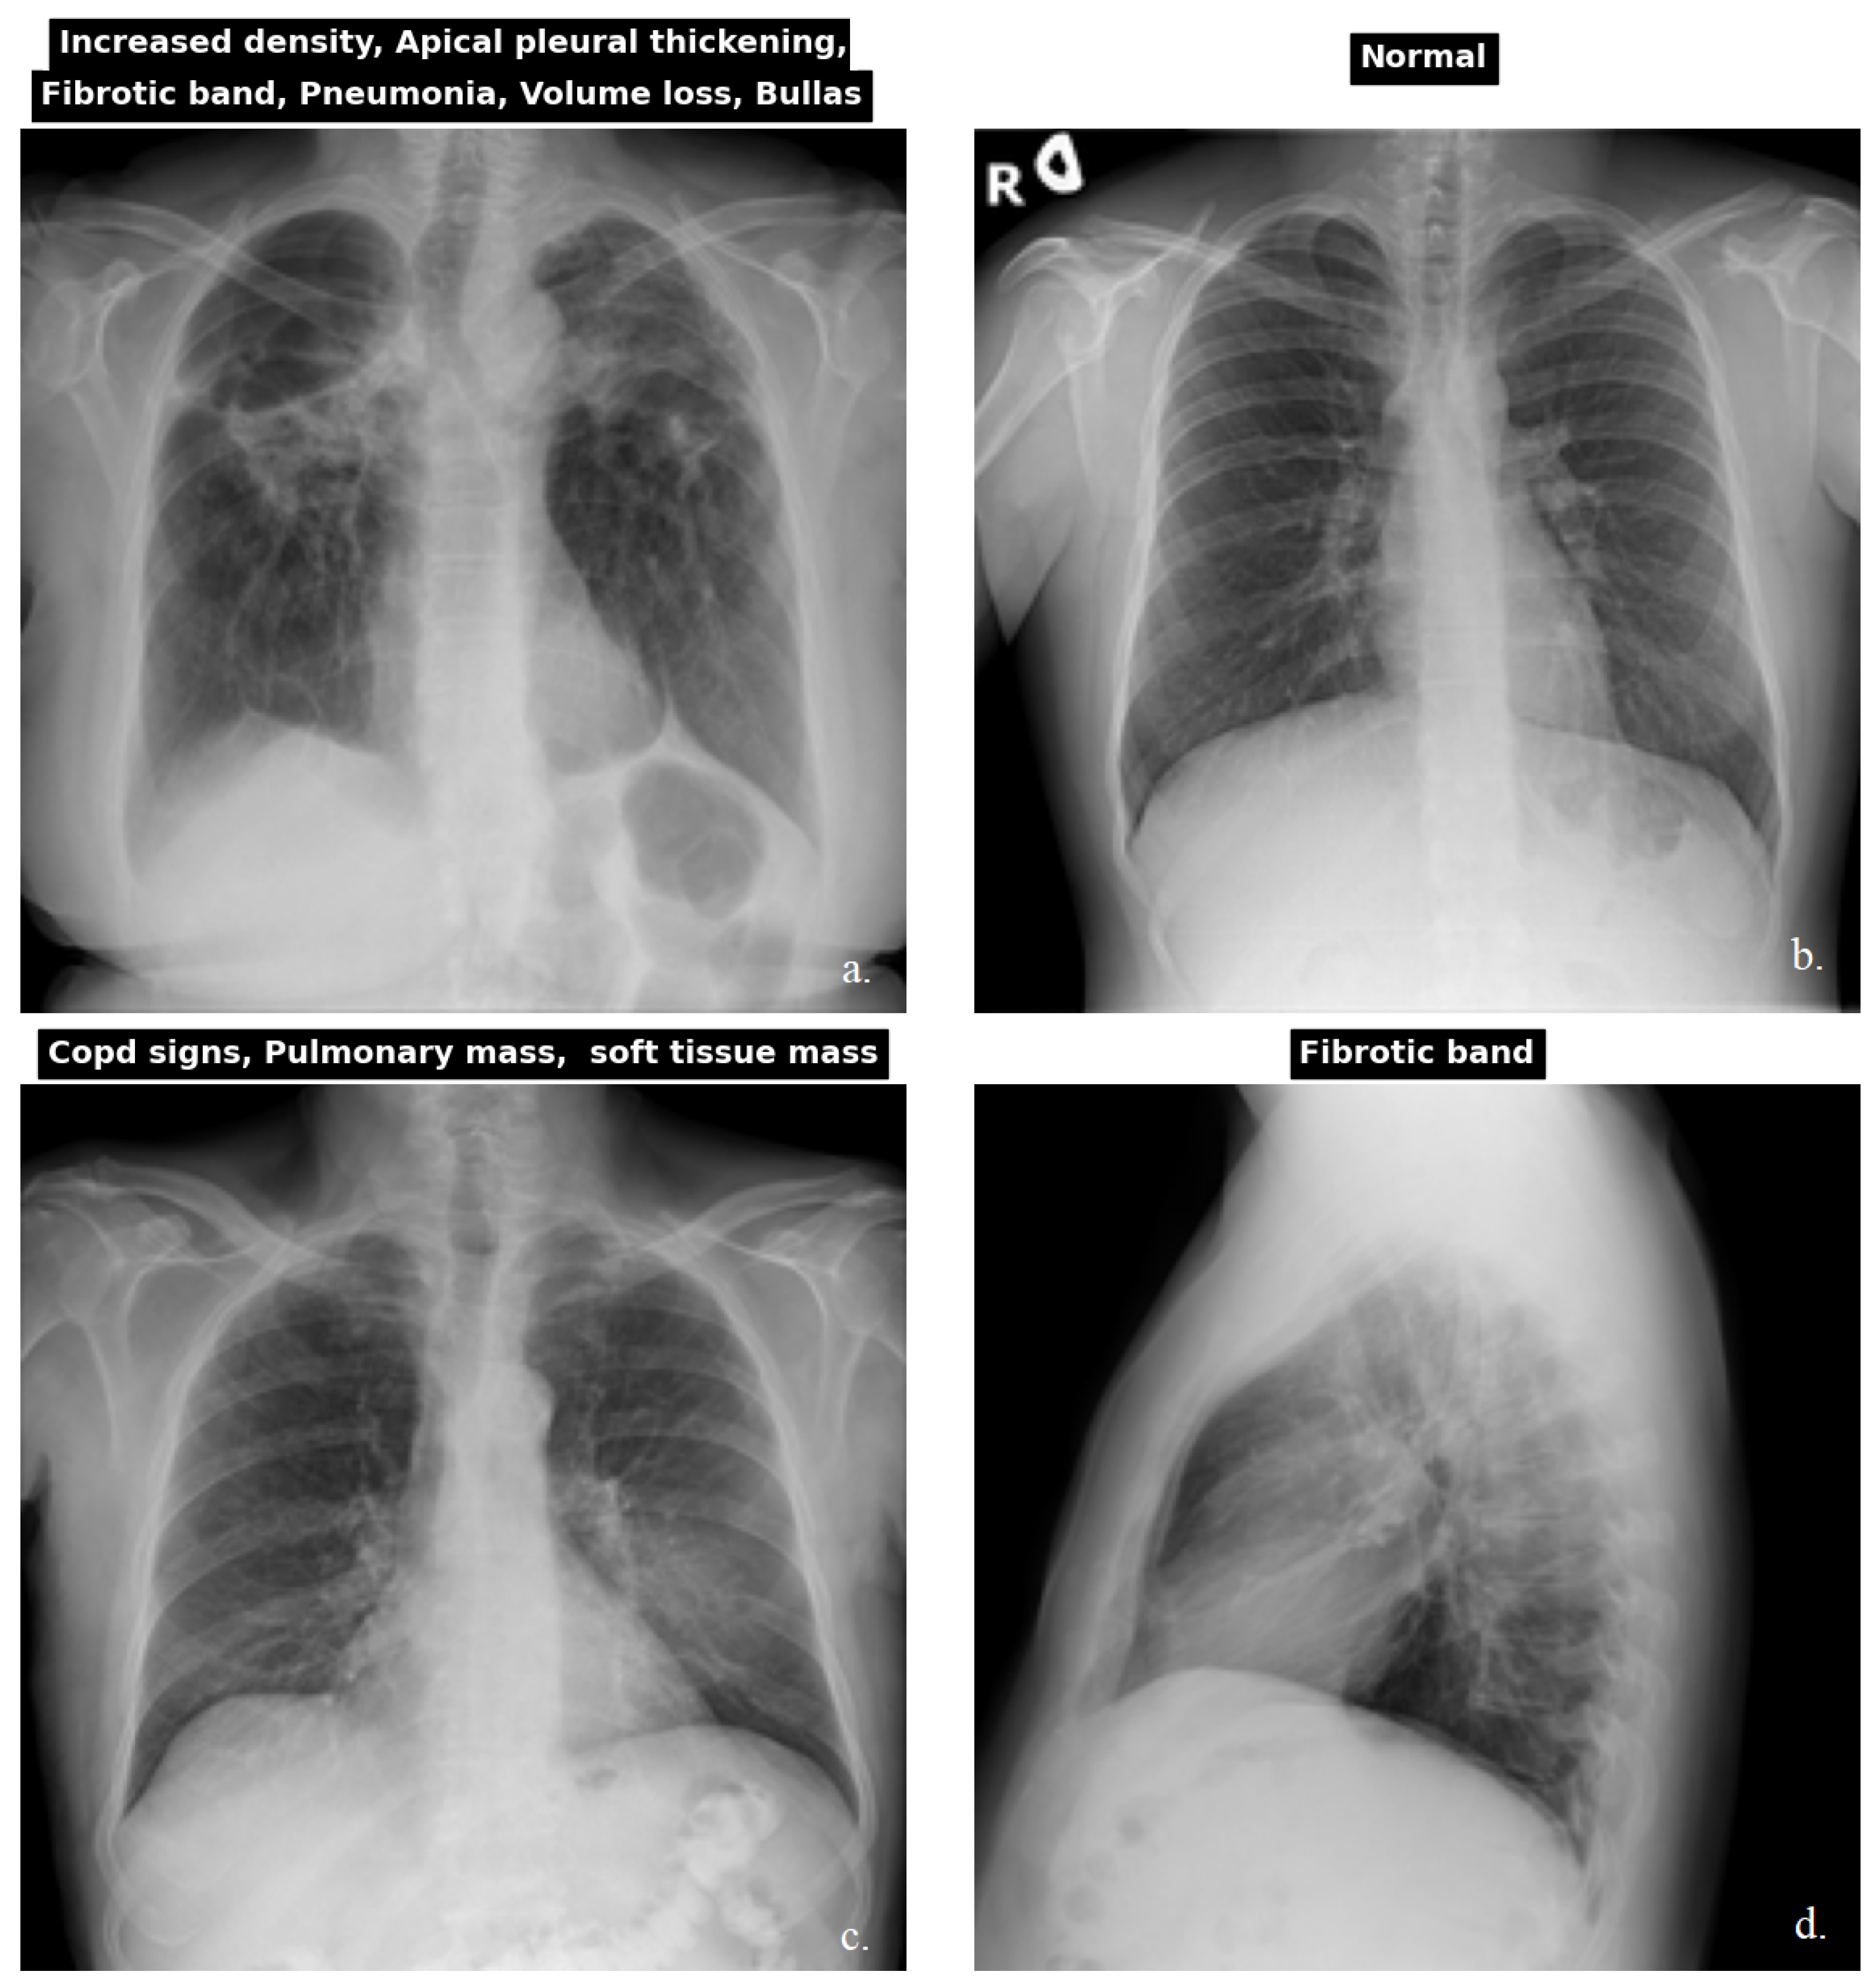

3.1.1. Dataset

- Wang, X.; Peng, Y.; Lu, L.; Lu, Z.; Bagheri, M.; Summers, R.M. Chestx-Ray8: Hospital-scale chest X-ray database and benchmarks on weakly-supervised classification and localization of common thorax diseases. In Proceedings of the 2017 IEEE Conference on Computer Vision and Pattern Recognition (CVPR), Honolulu, HI, USA, 21–26 July 2017; pp. 3462–3471. [Google Scholar] [CrossRef]

- CXR-PadChest. Available online: https://bimcv.cipf.es/bimcv-projects/padchest (accessed on 24 May 2025).

- Kermany, D.S.; Goldbaum, M.; Cai, W.; Valentim, C.C.S.; Liang, H.; Baxter, S.L.; McKeown, A.; Yang, G.; Wu, X.; Yan, F.; et al. Identifying medical diagnoses and treatable diseases by image-based Deep Learning. Cell 2018, 172, 1122–1131.e9. [Google Scholar] [CrossRef] [PubMed]